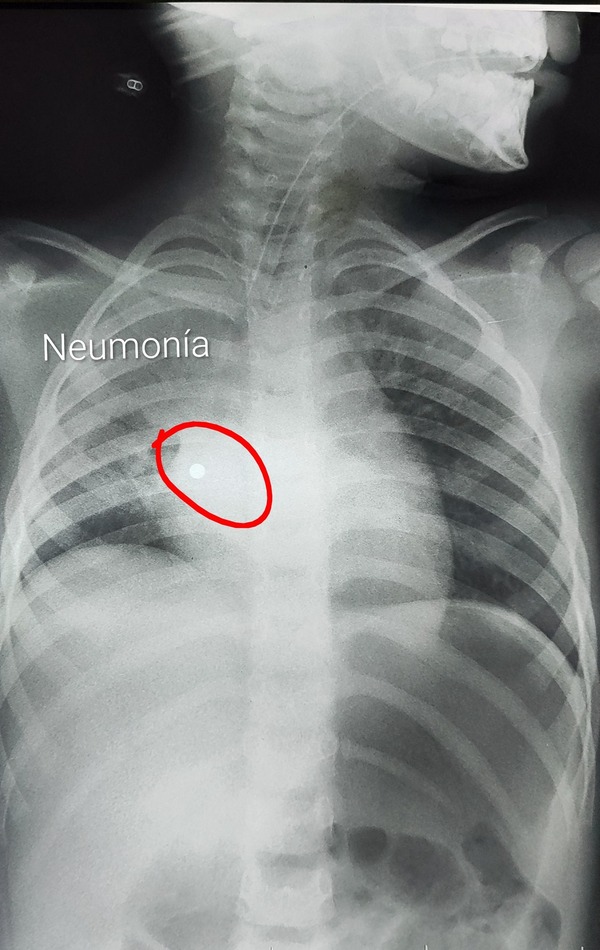

Desde el Ineram dieron a conocer el caso de una niña de 4 años, que sufrió una grave neumonía luego de haber aspirado la perla de un collar, que se alojó en el pulmón. ...[Leer más]